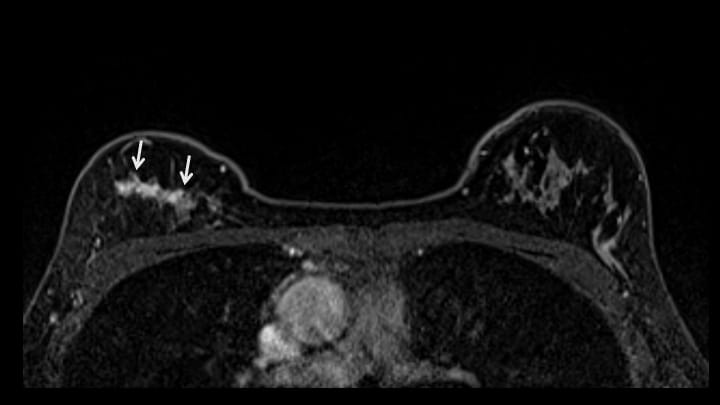

5. ダイナミックMRI 早期相

右乳腺上部にnon-mass enhancementを認める(矢印)。

8. ダイナミックMRI 後期相

早期相と同様に右乳腺上部にnon-mass enhancementあり。